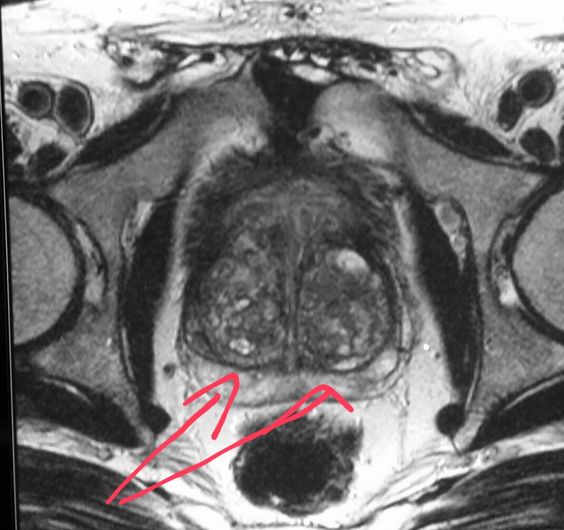

Пациенты часто задаются вопросом, что можно увидеть на МРТ малого таза и какие преимущества у данного метода? Вас могут беспокоить боли в области таза, зачастую это первые признаки серьёзных заболеваний. В этом отделе у человека расположен мочевой пузырь, женские репродуктивные органы и мужские половые органы, лимфатические узлы и кости таза. О причинах и симптомах мы расскажем чуть позже, ну а сейчас остановимся на МРТ исследовании. Что это за процедура и почему она важна для пациента? Магнитно-резонансная томография малого таза это детализированное изображение органов, тканей и крестца на снимке. Процедура необходима для тщательного и качественного обследования внутренних органов малого таза. МРТ позволяет получить информацию о структурных внутренних изменениях в тканях и первичных признаках опасных и серьезных заболеваний. По сравнению с СКТ, на снимках МРТ можно более детально изучить мягкие ткани и всевозможные патологические процессы в них. Вам выписали направление на обследование, но вы не знаете, где делают МРТ органов малого таза? У пациента всегда есть право выбора медучреждения. Сделать правильный выбор клиники и ознакомиться с положительными отзывами, всегда можно при помощи Интернет-ресурсов.

Результаты диагностики

После того, как диагностика закончена, пациент может быть свободен, а доктор-рентгенолог приступает к расшифровке результатов. Расшифровать МРТ малого таза грамотному рентгенологу не представляет труда. На имеющемся трехмерном изображении просматриваются четкие участки самых мельчайших патологических процессов, образований, просматриваются четкие границы и представляется возможность определить природу происхождений имеющихся новообразований, а также оценить состояние сосудов, лимфатических узлов и костной системы этой области. Всё это доктор-рентгенолог описывает в заключении к МРТ органов малого таза. По времени этот этап длится от 2 до 24 часов.

Какие патологии выявляет МРТ малого таза?

Рак шейки матки - это злокачественная опухоль расположенная на стенках канала шейки матки. Установить причину возникновения патологических изменений здоровых клеток (перерождение собственной клетки) не всегда удаётся. На самом деле они очень разнообразны. МРТ при раке шейки матки позволяет досконально обследовать и выявить наличие метастазов (распространение опухоли на другие органы). Не каждой женщине назначают МРТ, решение о проведении таковых обследований специалист принимает, опираясь на результаты детального осмотра и биопсии.

Патологические изменения репродуктивной системы женщины

Яичники в организме женщины — важный орган, в котором развиваются и созревают половые клетки. Говоря простым языком, благодаря им формируются яйцеклетка. Рак яичников - самое коварное заболевание, которое встречается у женщин после 45 лет. Его развитию способствует генетическая предрасположенность (если у матери был рак, то и у дочери впоследствии может обнаружиться это заболевание) или наличие доброкачественных наростов (папиллом). Для диагностики заболевания в редких случаях используют МРТ или КТ, изначально получают результаты биопсии (иссечение кусочка ткани или поражённого органа).

Освещая заболевания половых органов у женщины, следует сказать несколько слов ещё об одном заболевании. Дермоидная киста яичника — это нарост внутри яичников, в состав которого могут входить все ткани организма. К примеру вам сложно представить, что внутри вашего яичника может находиться комок волос или жировая ткань. Разрастаясь она вытесняет здоровые клетки яичника, тем самым нарушая нормальную работу органа.

Помимо злокачественной опухоли на матке может развиваться и доброкачественное новообразование, именуемое миома. Не впадайте в панику от диагноза миома матки. Такой вердикт не слишком опасен, при детальном осмотре врач визуально установит наличие нароста, но дополнительно отправит на УЗИ. После чего вам назначат медикаментозное лечение (приём препаратов) или удаление миомы.

Женские органы подвержены многим заболеваниям, очередным малоприятным недугом является эндометриоз. В процессе заболевания клетки эндометрия (внутренний слой) разрастаются внутри матки, тем самым образуя нарост. Распознают это заболевание при помощи визуального осмотра или при помощи УЗИ и МРТ.

Какие заболевания поражают мужские половые органы

Мужские половые органы, не меньше чем женские, поражаются различными заболеваниями. Самыми опасными из них являются раковые опухоли. Простата или предстательная железа — это второе сердце для мужчин. Патологическое изменение этого органа сулит мужчине нарушением работы мочеполовой системы в целом. Халатное отношение к своему здоровью в дальнейшем приводит к проблемам в сексуальной жизни мужчины. Мы не станем заострять внимание на причинах возникновения заболеваний.ю связанных с простатой, остановимся лишь на том, как и кто диагностирует наличие вредоносных болезней.

Имея на руках предварительные результаты диагностики, в которых указанно наличие раковой опухоли, вы можете обратиться в клиники, где проводят дополнительные обследования. Что может показать МРТ диагностика рака простаты, и какие выводы можно сделать из расшифровки? В ряде случаев такое обследование обусловленно наличием определённых признаков, к примеру один из них — увеличение простаты. Увеличение органа свидетельствует о наличии воспалительного процесса. В тех случаях, когда у вас существуют подозрение о наличии такого заболевания, как рак предстательной железы, МРТ обследование увеличивает шансы получения качественной и достоверной информации о заболевании.